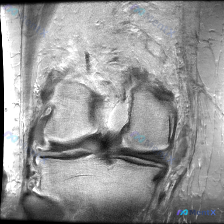

最近碰到一个有意思的病例:用户提示存在膝关节软骨异常,但提供的单张冠状位MRI却没有发现明确异常,整理一下分析思路和大家分享。 一、病例基础信息 这是一张单张膝关节MRI冠状位影像,分析可见: 1. 序列与解剖:为冠状位T2/质子密度加权序列,可显示股骨内外髁、胫骨平台、内外侧半月板及侧副韧带 2....